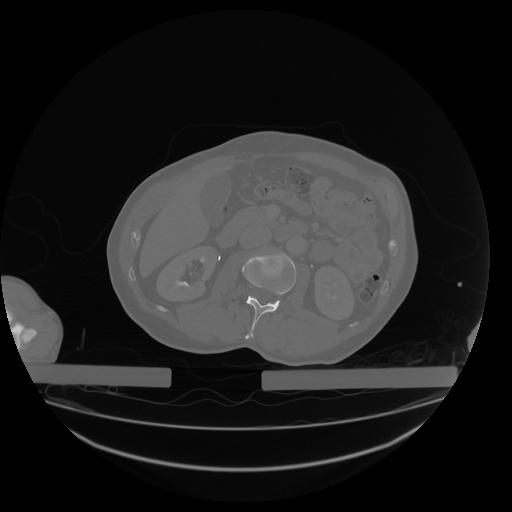

34 CUERPO,CE,Vol,1.0,CUERPO,,